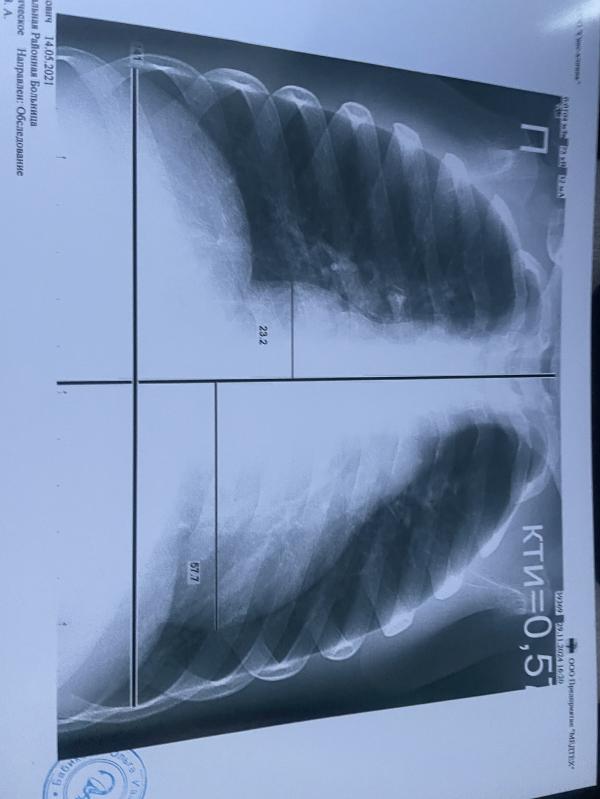

Съездили из-за кашля сделать рентген, а в итоге расширены границы сердца.

Было у кого-то так у детей? Что делали?